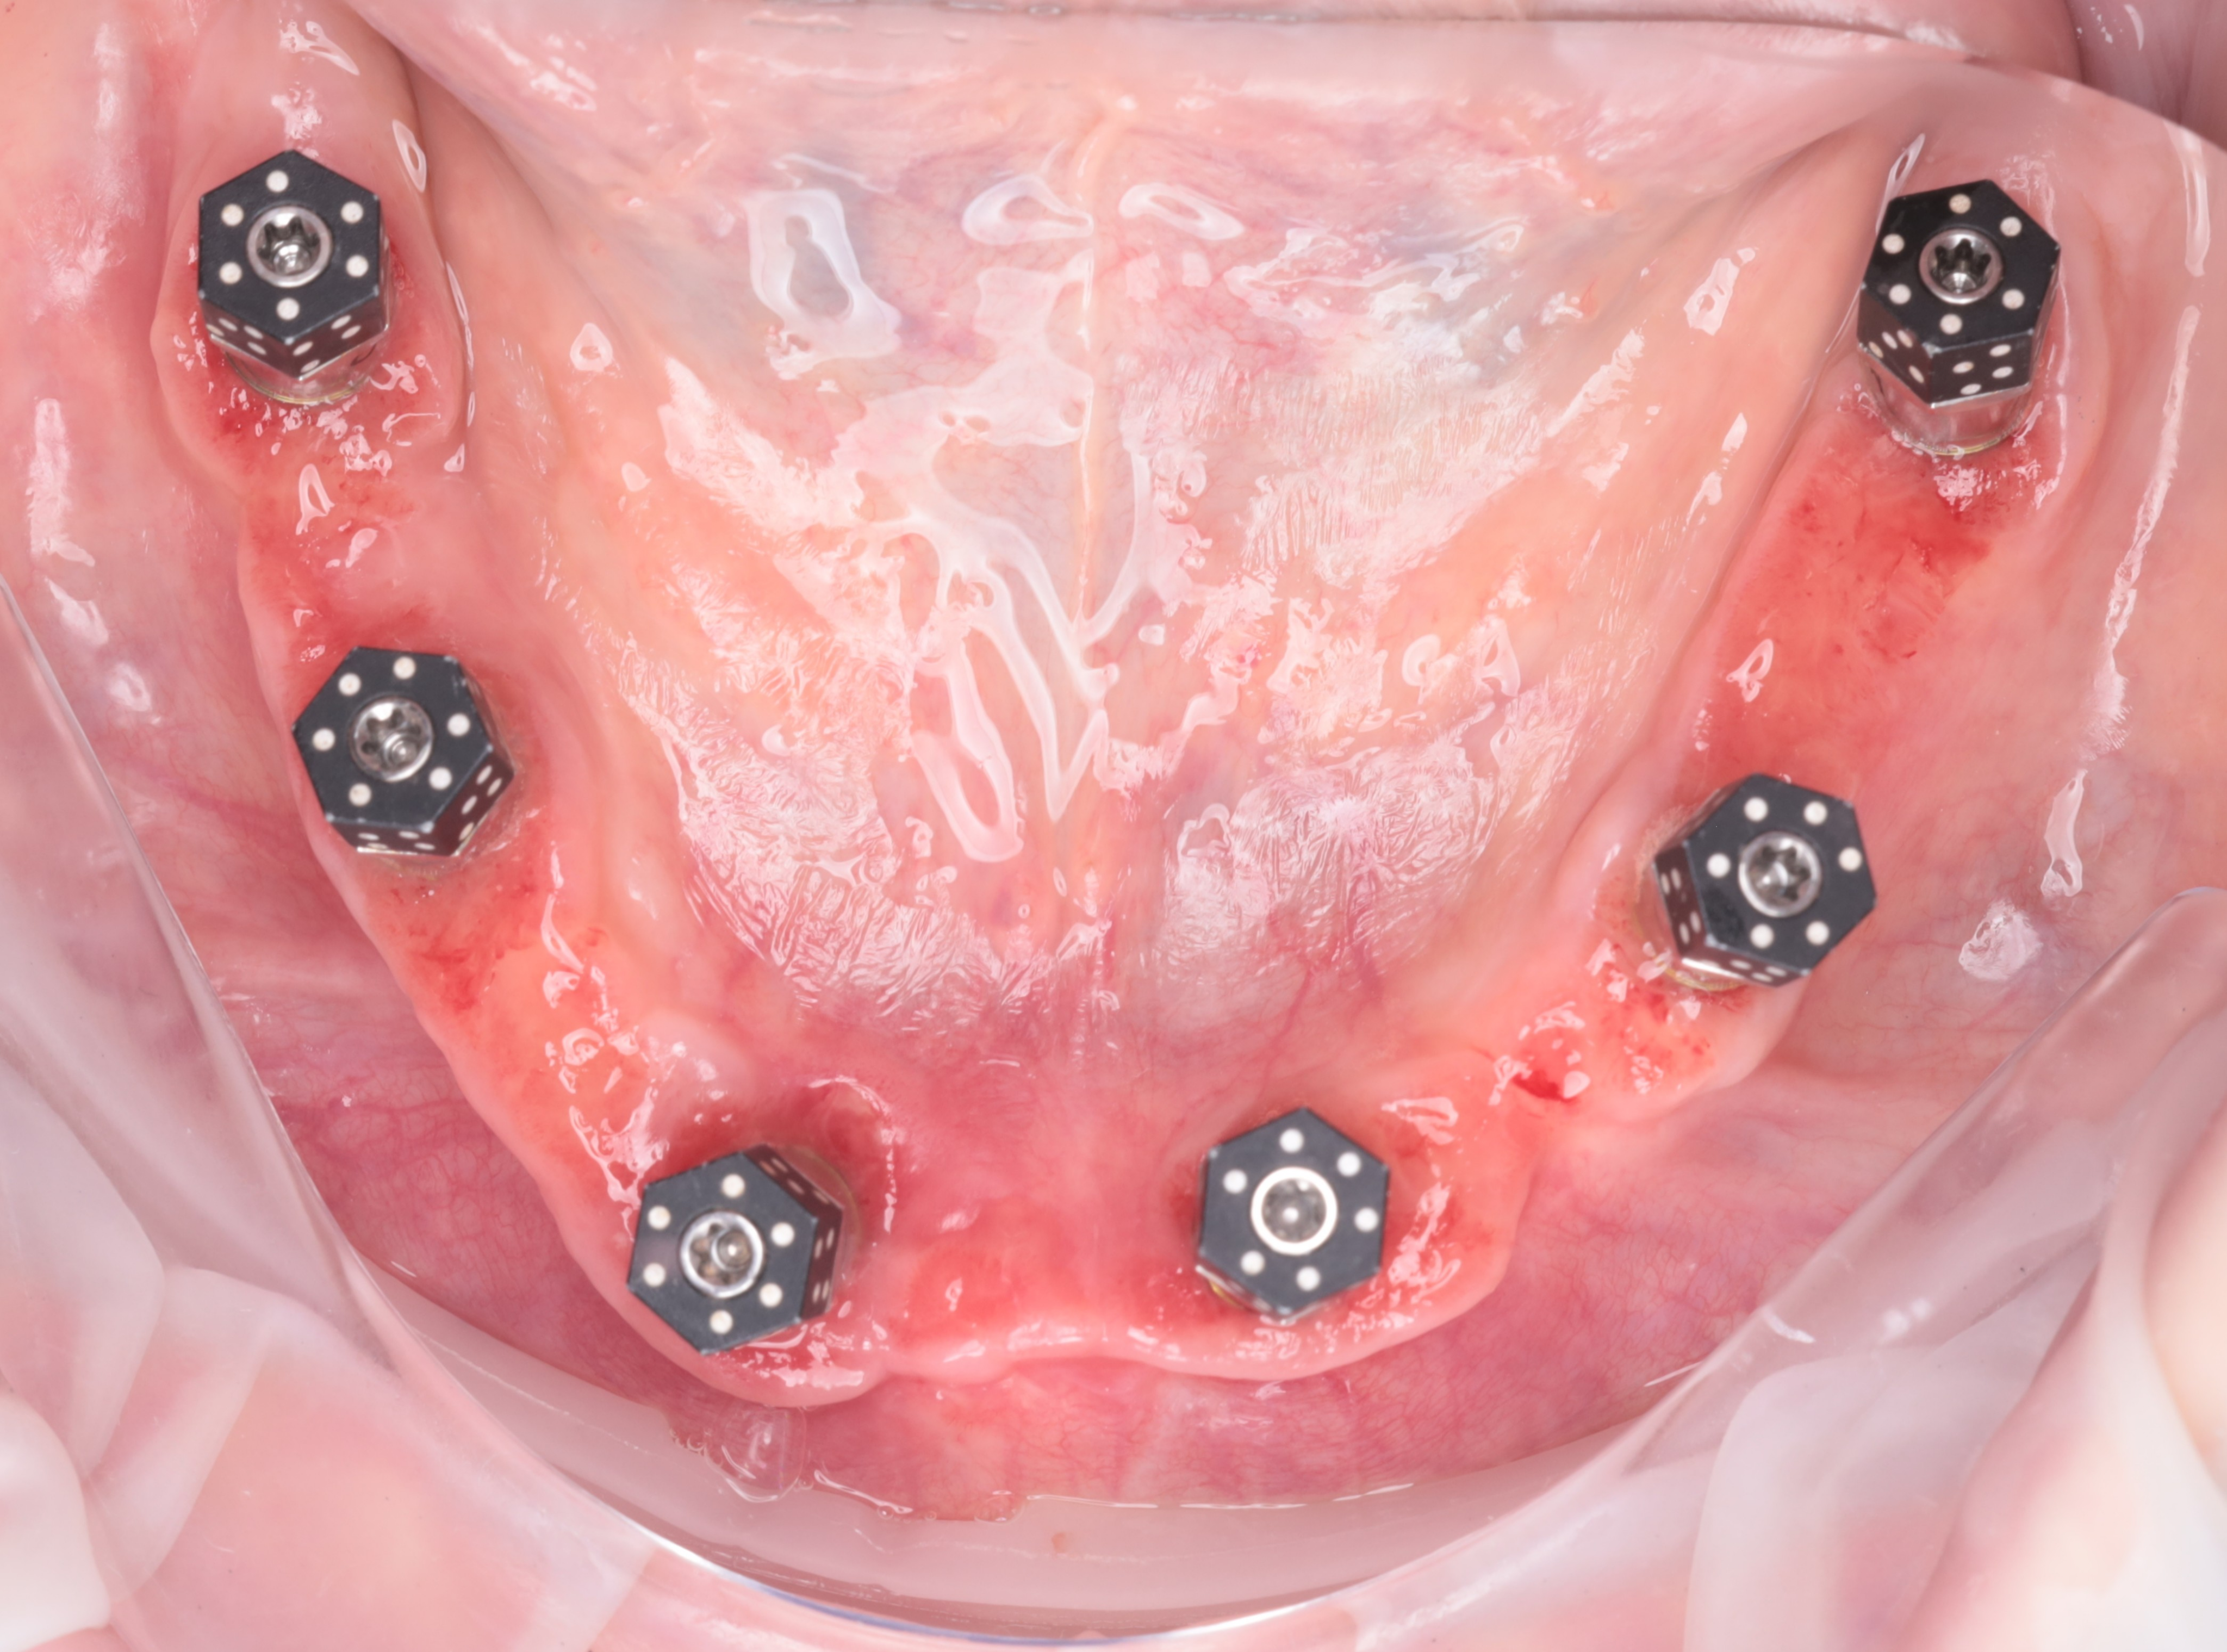

Digital Workflow and Immediate Loading

The digital workflow for this full arch dental implants case centered on the SHINING 3D Elite Intraoral Scanner equipped with IPG technology, which allowed for the rapid and high-precision capture of multi-unit implant positions and soft tissue. These precise data sets can also be integrated with pre-operative intraoral scans to provide an accurate occlusal reference for the provisional restorations.

Based on the high-fidelity digital impressions, same-day resin provisional prostheses were fabricated and delivered immediately after surgery. The precision of the IPG scan ensured a successful same-day provisional bridge delivery and secure retention using Rosen screws without the need for titanium bases. Post-operative Orthopantomogram (OPTG) confirmed accurate seating and stable connections across all implants, with a 2 mm occlusal clearance maintained in the molar region to ensure functional safety during the initial healing phase.